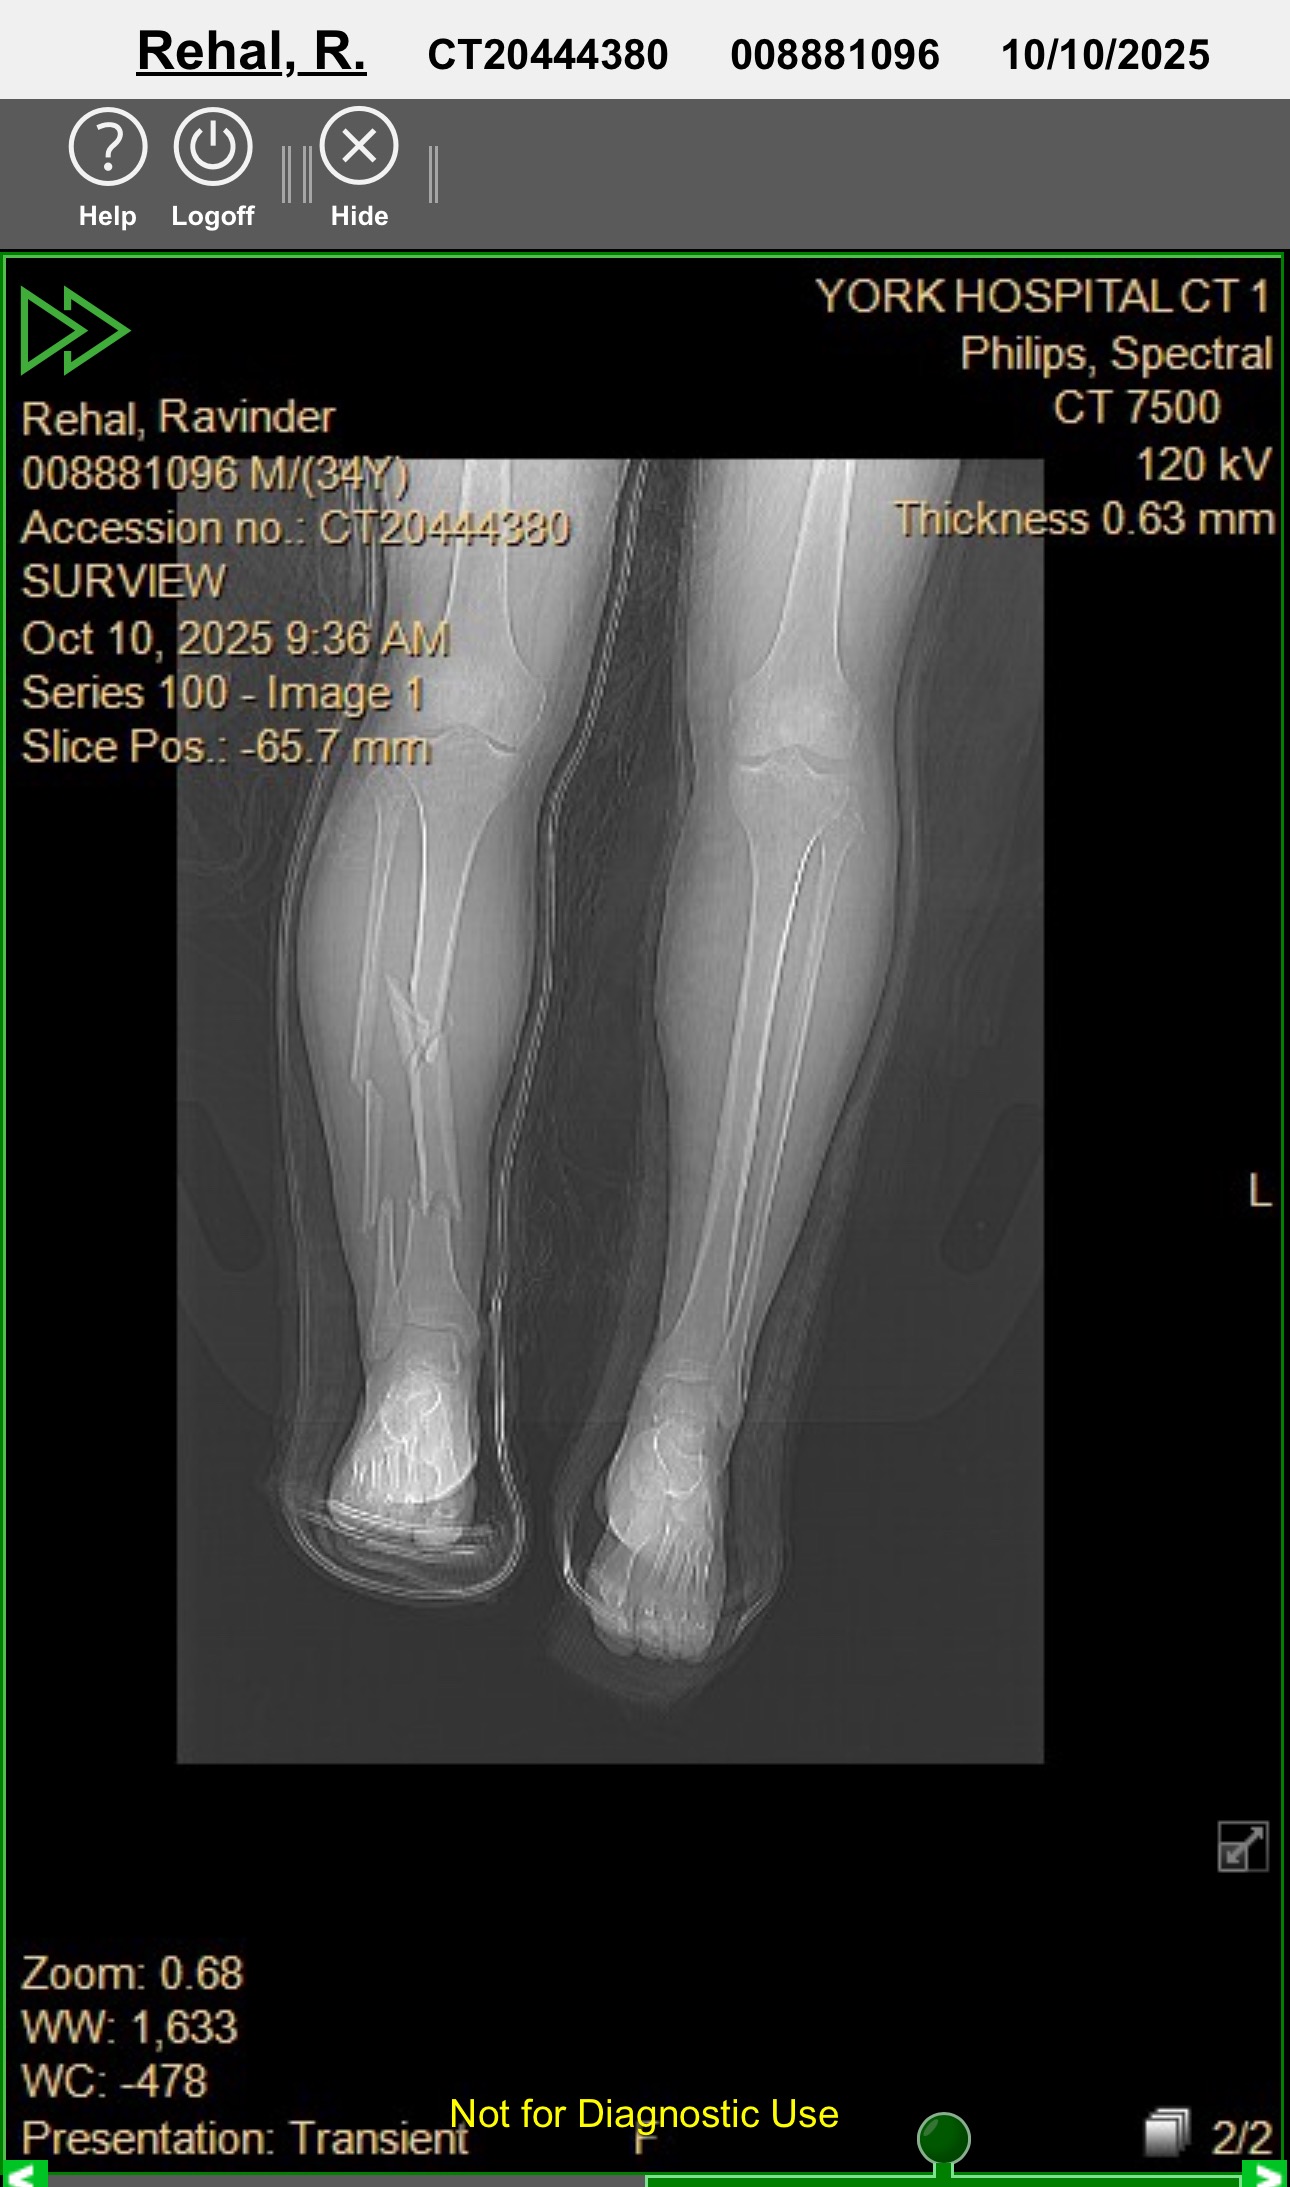

It was normal Friday morning on Oct 10 when I was crossing the road to grab a cup of coffee from a gas station in Green Castle, PA to kick start my day as I was excited to reach home early for the Thanksgiving long weekend. It was pretty drak at around 6:15 am when all of a sudden I got hit by a car out of no where and I fell on the street and was airlifted to a trauma center in York, PA. My both legs received a significant damage, severe injuries to my ribs and bruises all over my body. Doctor are looking at atleast 8weeks of Rehab before I can start putting weight on my feet and will be a long time before I can start working and living my life normally. I would like to request you to please help me with anything in these tough time. Your smallest of help will be blessing for me and my family.